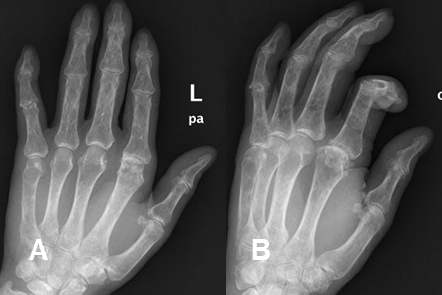

Las alteraciones metabólicas se manifiestan radiológicamente, en las diferentes modalidades diagnósticas, como osteopenia u osteoesclerosis. (Fig 44 A y 44 B).

Fig 44 A. Insuficiencia renal crónica y diabetes.

A: Rx AP y B: Rx oblicua. Alteración en la densidad ósea, con osteopenia generalizada, en un paciente con insuficiencia renal crónica.